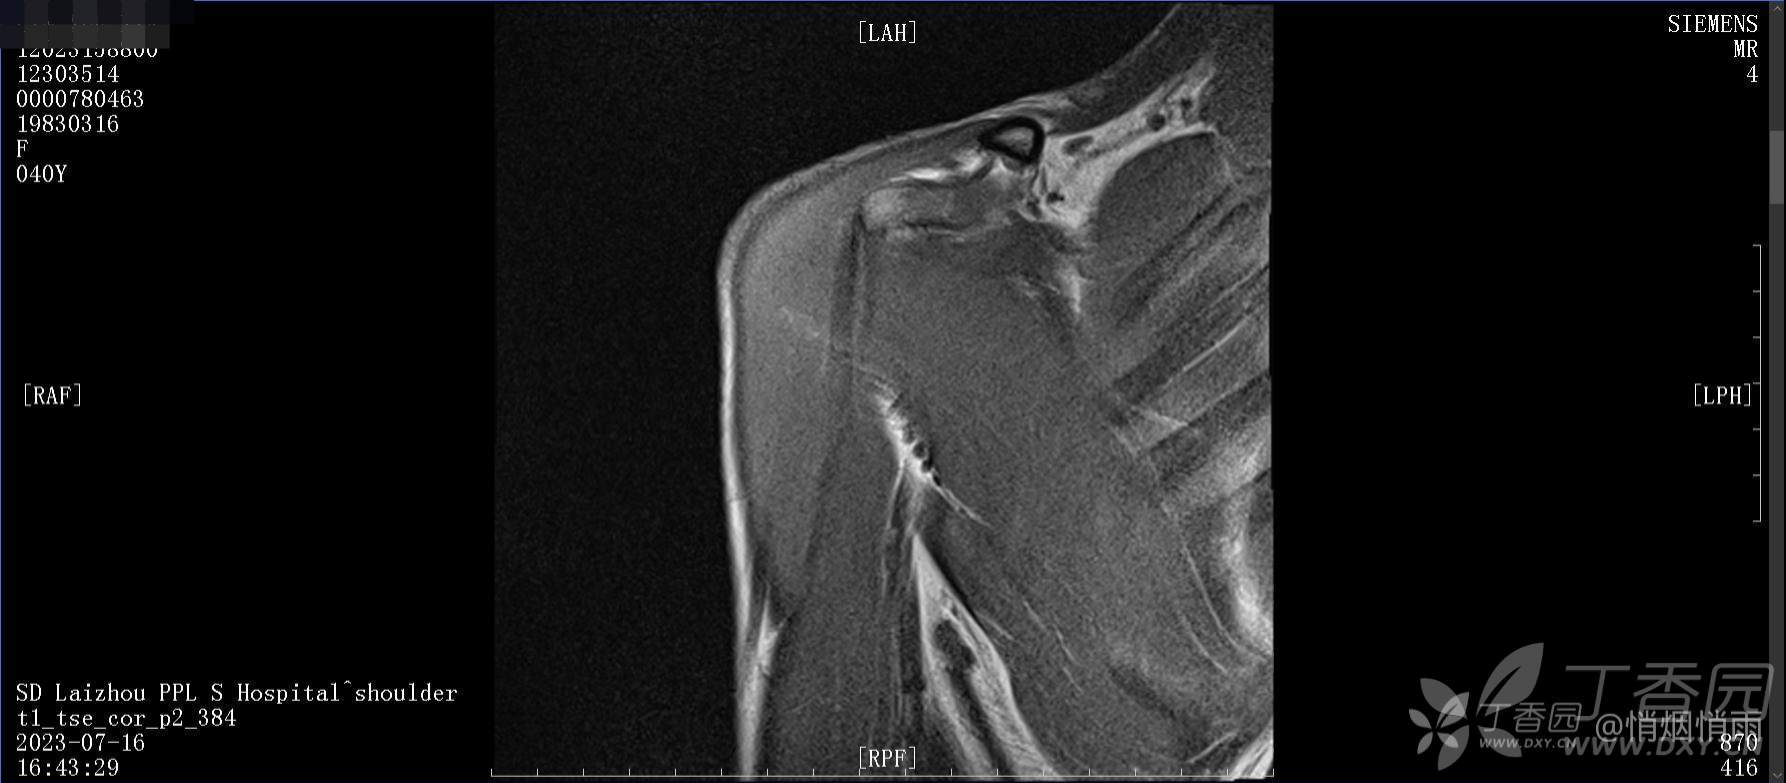

查体:右肩关节局部轻度肿胀,肩胛区压痛明显,痛处不固定,肩关节痛性活动受限,jobe test(+),lift -off test(+),中指、环指感觉较余指减退,余肢端感觉及血运情况可。

目前的诊断,暂时依据辅助检查诊为肩袖损伤,但是患者疼痛的性质和特点,却不是单纯的肩袖损伤所致。考虑过胸廓出口综合征,但是该疾病会出现肩胛区的疼痛吗?(由于考虑到费用的问题,没再进行下一步的检查)带状疱疹会有如此的症状吗?